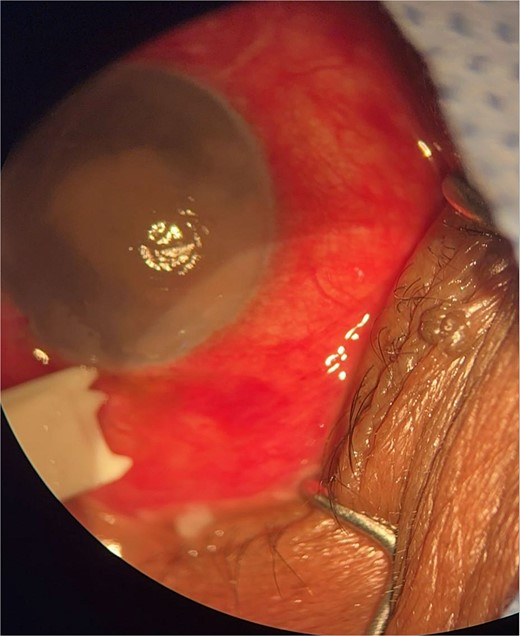

Patient 1: A 66-year-old Sudanese male presented to the emergency room with severe pain in his right eye 2 days post-phacoemulsification. Examination revealed only light perception, elevated intraocular pressure (IOP), a hazy cornea, hypopyon, and extensive pupillary membrane (Fig. 1). A B-scan ultrasound (Fig. 2). He underwent a vitreous tap and received intravitreal antibiotics.

B-scan ultrasound demonstrating mild to moderate vitritis in endophthalmitis case in patient 1.